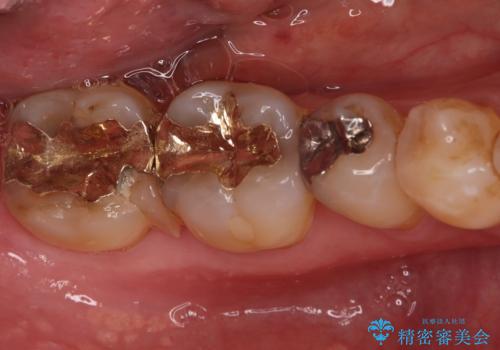

治療ではまず、欠けた部分を修復し、歯全体を均一に形成しました。その後、PGA(白金加金)クラウンを作製・装着しました。

PGAクラウンは、金(Gold)を主成分とする合金でできており、非常に優れた特性を持っています。

強度: 非常に高い強度を持つため、奥歯の強い咬合力にも耐え、歯の破折を効果的に防ぎます。

適合性: 歯への適合性が非常に高く、精密に隙間なく装着できるため、被せ物の下からの二次的な虫歯のリスクを最小限に抑えられます。